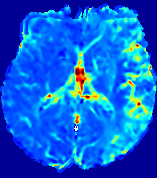

LesionRefer to captionRefer to captionRefer to captionRefer to captionRefer to captionRefer to caption𝐕rgbsubscript𝐕𝑟𝑔𝑏{\bf{V}}_{rgb}Refer to captionRefer to captionRefer to captionRefer to captionRefer to captionRefer to caption𝐕2subscriptnorm𝐕2{\|\bf{V}}\|_{2}Refer to captionRefer to captionRefer to captionRefer to captionRefer to captionRefer to captionRefer to caption3.53.53.52.82.82.82.12.12.11.41.41.40.70.70.70.00.00.0(mm/s)𝑚𝑚𝑠(mm/s)D𝐷DRefer to captionRefer to captionRefer to captionRefer to captionRefer to captionRefer to captionRefer to caption0.0200.0200.0200.0160.0160.0160.0120.0120.0120.0080.0080.0080.0040.0040.0040.0000.0000.000(mm2/s)𝑚superscript𝑚2𝑠(mm^{2}/s)Slice #1Slice #2Slice #3Slice #4Slice #5Slice #6

Figure 4: PIANO feature maps for another patient in the ISLES 2017 training set, where the lesion is located in the right hemisphere. Top row: segmented stroke lesion region (white) on different slices. The corresponding slices for the PIANO feature maps are shown in the following rows.

For a better insight into an estimated velocity field 𝐕𝐕{\bf{V}} and diffusion field 𝐃𝐃{\bf{D}}, we compute the following maps: (1) 𝐕rgbsubscript𝐕𝑟𝑔𝑏{\bf{V}}_{rgb}: Color-coded orientation map of 𝐕=(Vx,Vy,Vz)T𝐕superscriptsuperscript𝑉𝑥superscript𝑉𝑦superscript𝑉𝑧𝑇{\bf{V}}=(V^{x},V^{y},V^{z})^{T}, obtained by normalizing 𝐕𝐕{\bf{V}} to unit length and mapping its 3 components to red, green, blue respectively; (2) 𝐕2subscriptnorm𝐕2\|{\bf{V}}\|_{2}: 222 norm of 𝐕𝐕{\bf{V}}; (3) D𝐷D: scalar field in Eq. 5.

Fig. 3 and Fig. 4 show the PIANO feature maps estimated from two ISLES 2017 patients: all are highly consistent with the lesion in both cases. Details of the blood flow trajectories are revealed in 𝐕rgbsubscript𝐕𝑟𝑔𝑏{\bf{V}}_{rgb} by the ridged patterns and the sharp changes of colors in the unaffected (right) hemisphere, while the flat patterns appearing within the lesion provide little directional information about the velocity and indicate low velocity magnitudes. Velocity magnitudes are more directly visualized via 𝐕2subscriptnorm𝐕2\|{\bf{V}}\|_{2}, from which one can easily locate the lesion where 𝐕2subscriptnorm𝐕2\|{\bf{V}}\|_{2} is low. D𝐷D also indicates lower diffusion values in the lesion, though with less contrast potentially due to the fact that it captures the accumulated effect of CA diffusion at the voxel-level.